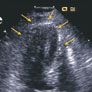

This patient remained asymptomatic during the remainder of her hospitalization. Dosages of the ACE inhibitor and β-blocker were limited because of hypotension, and the ACE inhibitor was ultimately withdrawn. A second ECG on hospital day 2 showed normal sinus rhythm with resolution of the ST-segment elevation. After 48 hours, she was discharged with a regimen of metoprolol succinate, sublingual nitroglycerin, and simvastatin. Seven days after discharge, echocardiographic studies continued to show abnormal left ventricular systolic function with an ejection fraction of 41% and grade 1 diastolic dysfunction. A follow-up echocardiogram 3 weeks later showed resolution of the apical wall motion abnormality (arrows) and an ejection fraction of 76% (C).